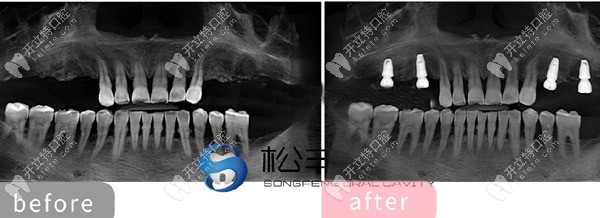

★ 多顆牙齒缺失種植展示

多顆牙齒缺失種植展示

★ 上半口做了6顆即刻負(fù)重種植牙的CT片

上半口做了6顆即刻負(fù)重種植牙的CT片